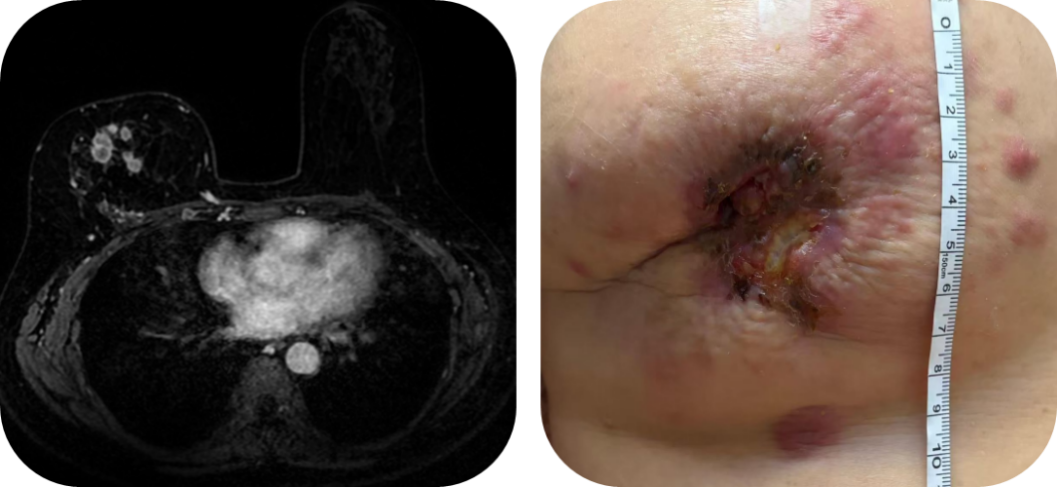

体格检查(2025年7月22日):右侧乳腺皮肤暗红,可见约3×2cm破溃,周围伴有皮下结节及黑色结痂。下方可触及约2×1cm质硬肿物,活动度差。右腋下可触及肿大淋巴结。

疾病进展 (2025.01.22): 评估显示右乳病灶再次增大并出现破溃。

疾病进展 (2025.05.22):患者病情急剧恶化,右乳病灶破溃增大,皮下结节增多。

疗效评估(2025.7.22):治疗2疗程后,疗效评估为PR 。患者胸壁破溃病灶基本愈合,肺转移灶消失。